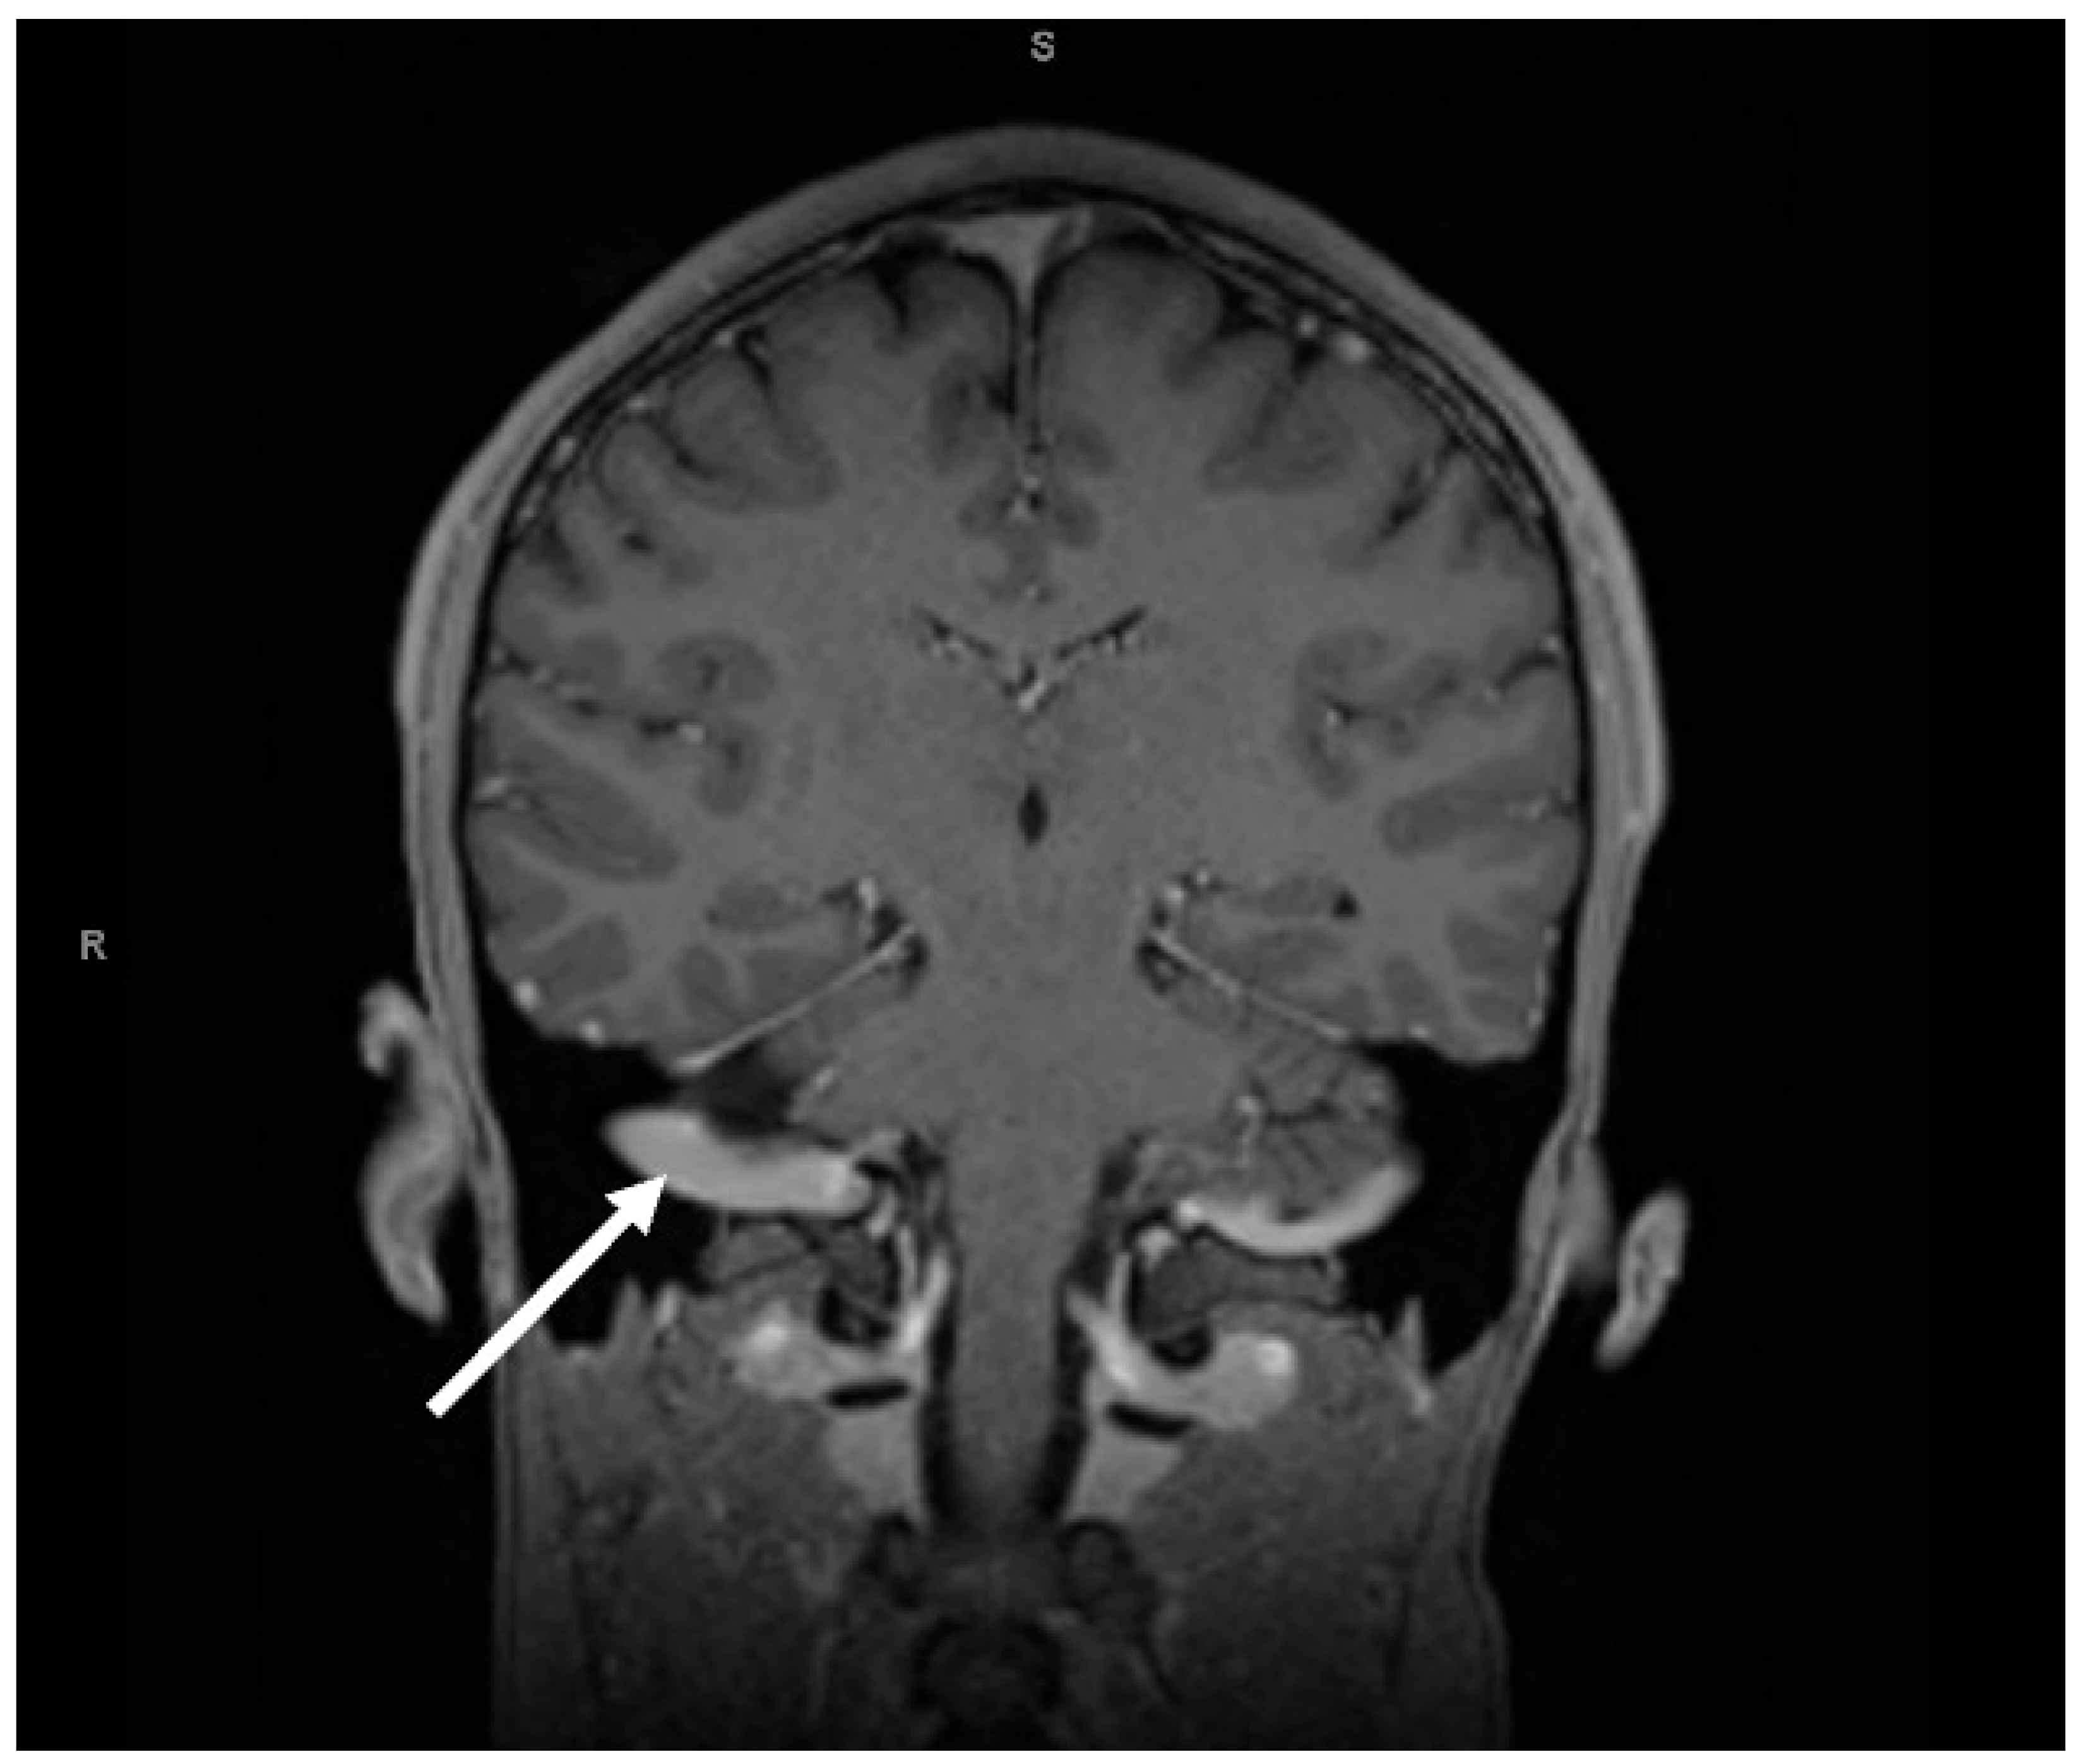

2. Case Presentation